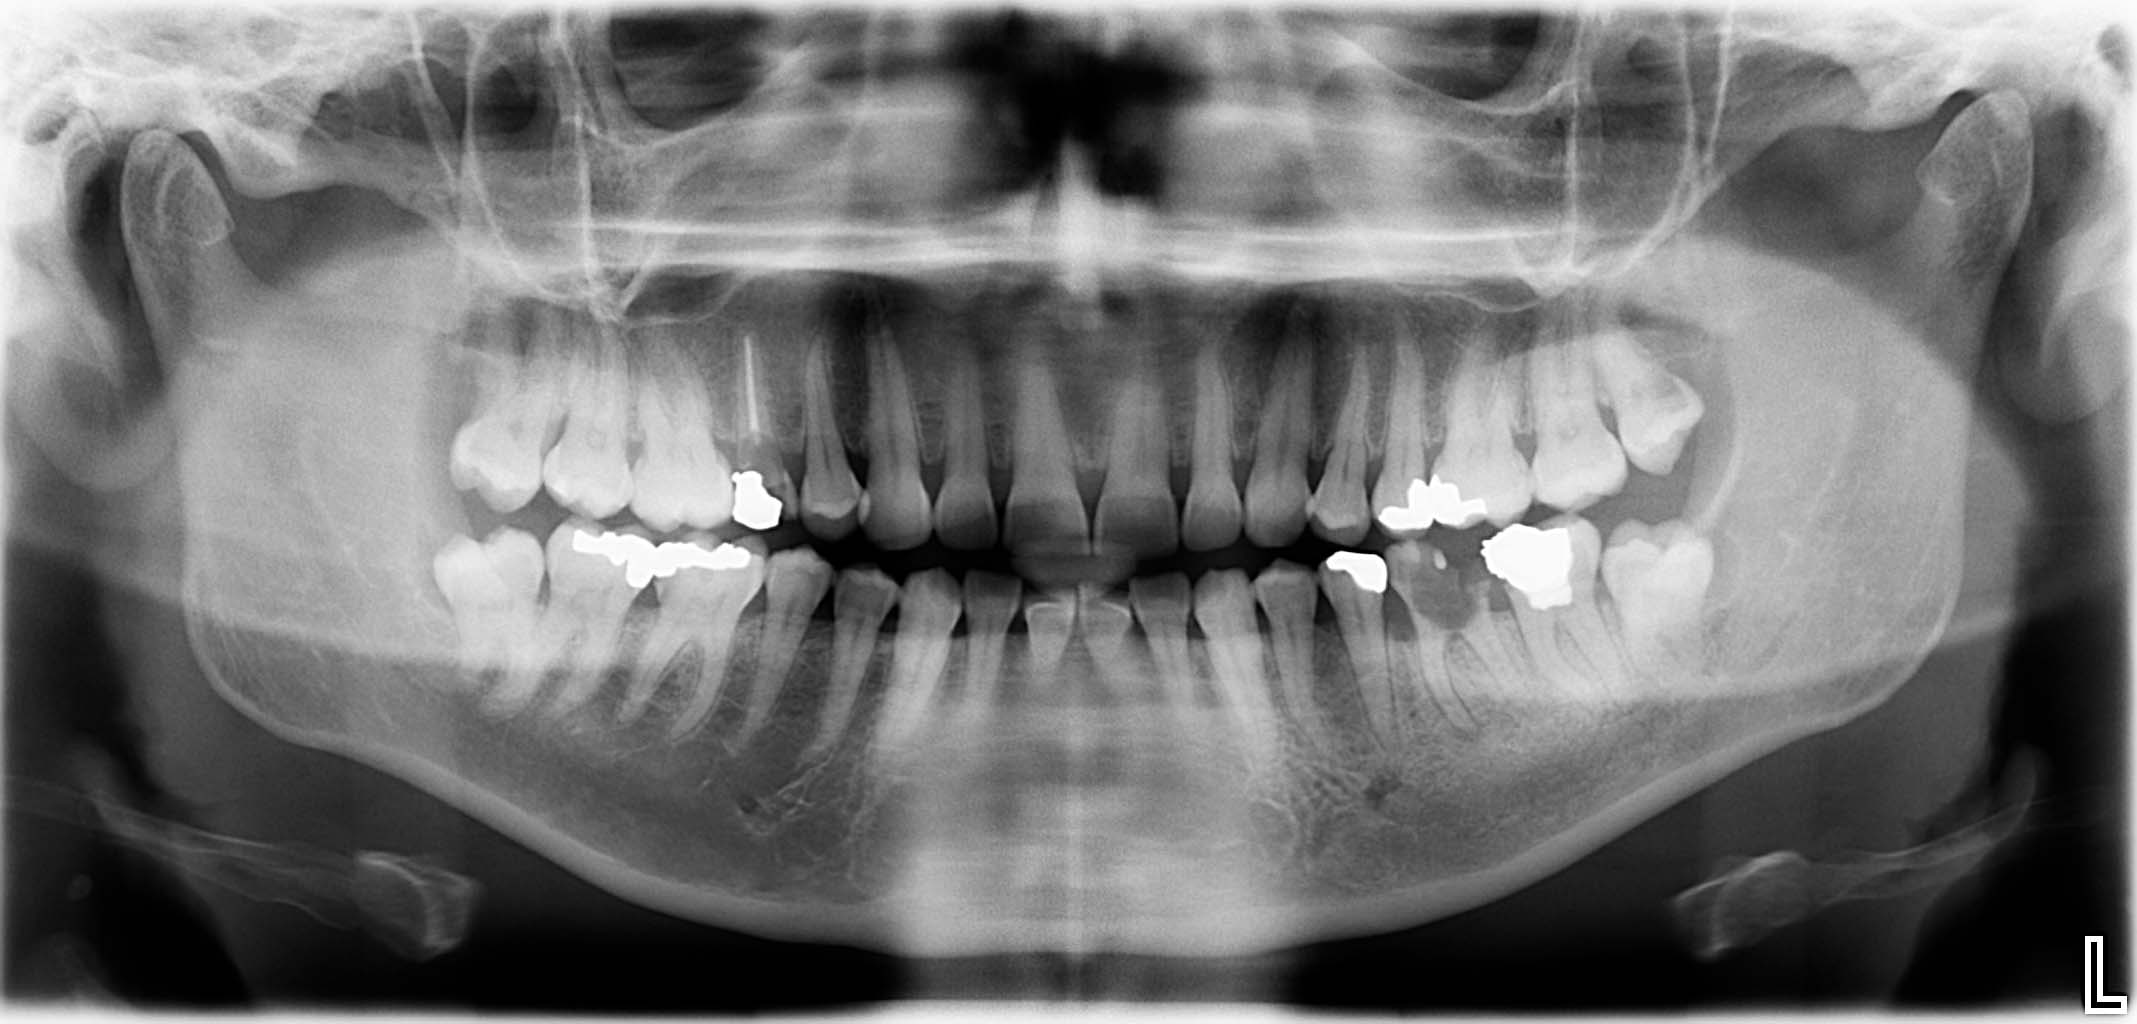

Ausgangssituation: Zahn 36 mit apikaler Beherdung, nicht erhaltungswürdig